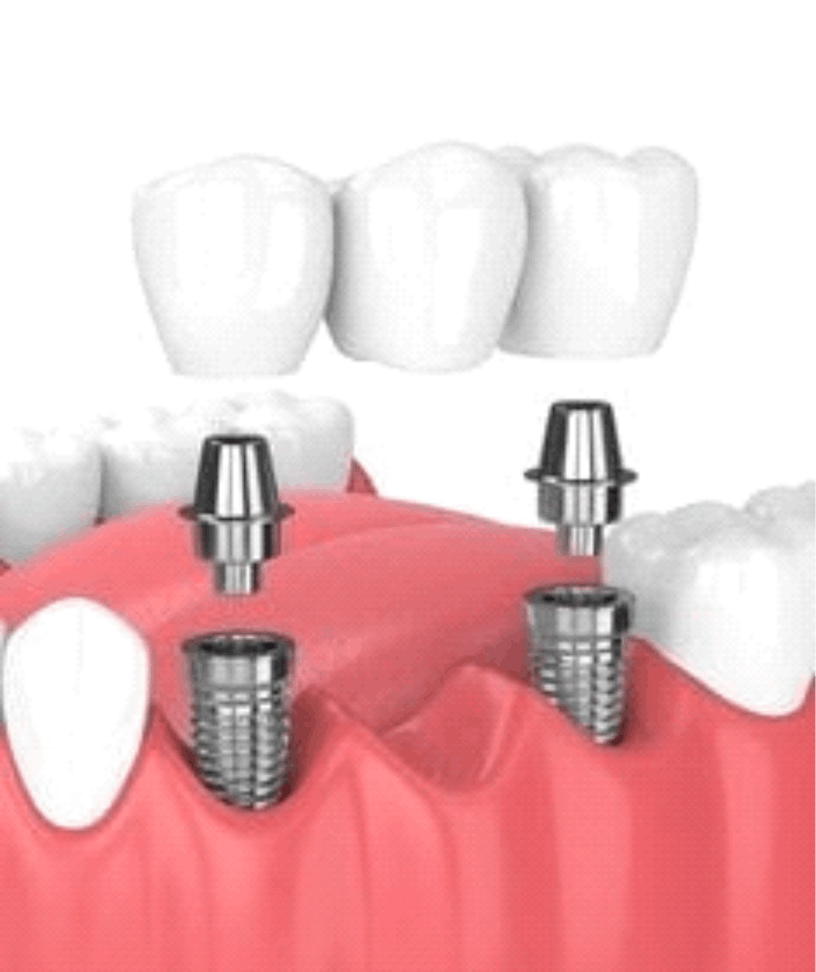

Para se submeter a um implante dentário, o paciente deve ter uma boa saúde bucal, ossos mandibulares saudáveis e estar livre de doenças periodontais ativas. Uma avaliação odontológica é necessária para determinar a viabilidade do implante.

O procedimento é realizado sob anestesia local, o que minimiza qualquer desconforto durante a cirurgia. Algumas pessoas podem sentir um leve desconforto após a cirurgia, mas isso pode ser controlado com analgésicos recomendados pelo dentista.